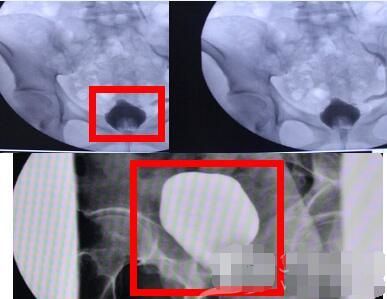

6、尿频、尿急、尿痛,甚至尿血是长期滥用*粉K**的人最常见、最典型的症状,这是因为*粉K**作为一种白色结晶粉末,通过鼻子吸入体内后,约90%经肾排泄,5%随粪便排除,还有5%会以原型通过泌尿系统排出。

这5%的原型细结晶体粉状,不仅一路刮伤输尿管内壁,更会导致膀胱炎、膀胱挛缩,严重时可以致使膀胱挛缩至正常人的十分之一(所以无法储存像正常人一样储存过多尿液,导致尿频、尿急),这在医学上叫典型的氯胺酮相关性膀胱炎。